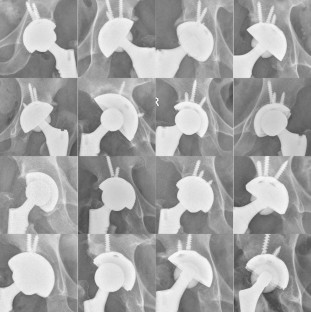

The results of the three measuring persons were completely identical in 61.8% (251/406) of cases, and the variation in 38.2% (155/406) of cases did not exceed one size of the acetabular cup. The Kendall’s W coefficient was 0.977, and p < 0.01. The measurement accuracy is not as good as the traditional method in exactly accurate measurement and ±1 cup size, but it is similar to the traditional method in the ±2 cup sizes. The correlation between the templating error and the position evaluation of the implanted acetabular cups reveals: (1) larger the templating error, larger the proportion of the acetabular cups with poor position; (2) the proportion of acetabular cup with poor position slowly increased when the templating error was from 0 to 1 size, and the proportion rapidly increased when the templating error was from 1 to 2 size.

All the patients with clear teardrop bottom and lateral superior edge of acetabulum were able to use our method to predict the size of the acetabular cup. The method has the following advantages: (1) it does not require the measuring person to have any previous experience of the THA surgery, which reduces the labor cost of the templating; (2) the differences between the measuring persons is small, the measurement result can be repeated; (3) it can predict the probability of acetabular cup with poor positioning according to the templating error, and thereby reminding the surgeon to recheck and correct the position of the acetabular cup in time during the surgery.